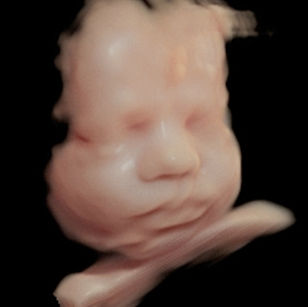

Weight: ~2.75 pounds (1.25 kg), the size of a Butternut Squash!

Length: ~15.2 inches (38.5 cm)

Development Highlights:

Brain continues rapid growth; folds are increasing.

Eyes can open and respond to light.

Fat continues to accumulate, smoothing out wrinkled skin.